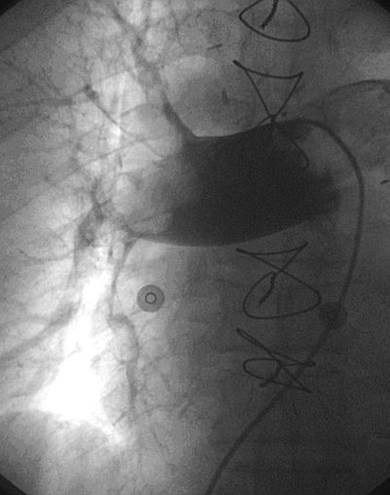

Trombectomía de la arteria pulmonar derecha

Angiografía de la arteria pulmonar derecha realizada con un catéter en espiral de 6 F en ángulo, que demuestra la presencia de un trombo de gran tamaño dentro de la arteria pulmonar derecha y en las bifurcaciones lobulares intermedia, inferior y superior.

Se efectuó una trombectomía reolítica con el catéter PE de AngioJet® mediante un catéter guía multifunción de 8 F y una guía de angioplastia hidrófila de 0,035’’, en las bifurcaciones lobulares intermedia e inferior.

Angiografía pulmonar derecha realizada tras una trombectomía reolítica en la que se muestra la mejora de los índices de perfusión y obstrucción.